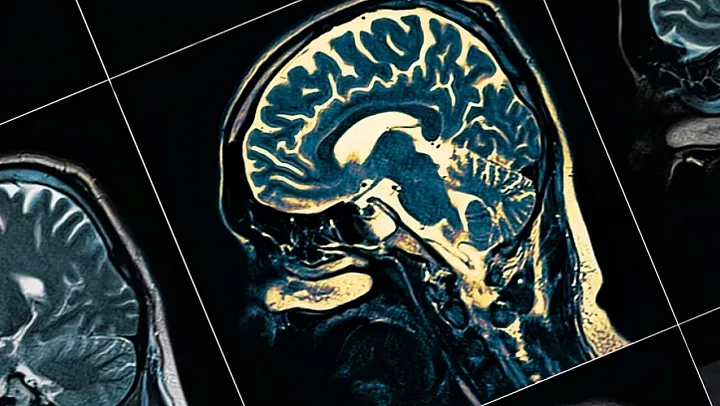

Alzheimer hastalığı, hem dünyada hem de Türkiye'de hızla artan hasta sayısıyla birlikte önemli bir halk sağlığı sorunu olmaya devam ediyor. Günümüzde kesin bir tedavisi bulunmayan bu nörodejeneratif hastalık için uygulanan yöntemler daha çok belirtileri hafifletmeye ve hastalığın ilerleme hızını düşürmeye odaklanıyor. Son yıllarda ise bilim dünyasında, beslenme alışkanlıklarının beyin sağlığı üzerindeki etkisi giderek daha fazla gündeme geliyor. Özellikle farklı ülkelerde yürütülen ve toplamda on klinik çalışmanın verilerini değerlendiren araştırmalar, belirli bir diyet modelinin Alzheimer hastalarında beyin fonksiyonlarını olumlu yönde etkileyebileceğini ortaya koydu.

Alzheimer, demans vakalarının en yaygın nedeni olarak biliniyor ve dünya genelinde yaklaşık elli beş milyon kişiyi etkiliyor. Türkiye'de ise bu sayının yedi yüz binin üzerinde olduğu tahmin ediliyor. Hastalığın temel özellikleri arasında hafıza kaybı, bilişsel işlevlerde gerileme ve günlük yaşam aktivitelerinde zorlanma yer alıyor. Beyindeki sinir hücrelerinin zamanla işlevini yitirmesi, bu sürecin en önemli nedenlerinden biri olarak kabul ediliyor.

Son dönemde yapılan çalışmalar, Alzheimer hastalığında yalnızca genetik ve çevresel faktörlerin değil, metabolik süreçlerin de belirleyici rol oynadığını gösteriyor. Beynin enerji üretiminde yaşanan aksaklıklar, sinir hücrelerinin sağlıklı çalışmasını zorlaştırıyor. Bu nedenle, beynin enerji ihtiyacını farklı yollarla karşılamayı amaçlayan beslenme yaklaşımları bilimsel araştırmaların odağına yerleşmiş durumda.

Sağlıklı bir beyinde temel enerji kaynağı glukoz olarak biliniyor. Ancak Alzheimer hastalığında, beynin glukozu yeterince verimli kullanamadığı bilimsel olarak ortaya konmuş durumda. Bu durum, nöronların enerji açığı yaşamasına ve zamanla işlevlerini kaybetmesine yol açabiliyor. Araştırmalar, keton cisimciklerinin bu noktada beyin için daha kolay erişilebilir bir enerji kaynağı sunduğunu gösteriyor.

Ketonlar, glukoza kıyasla beyin hücreleri tarafından daha rahat kullanılabiliyor ve enerji üretimini destekleyebiliyor. Klinik çalışmalardan elde edilen veriler, ketojenik diyet uygulayan Alzheimer hastalarında bazı bilişsel işlevlerin korunabildiğini ve beyin fonksiyonlarında olumlu değişimler gözlemlendiğini ortaya koyuyor. Bu durum, diyetin hastalığın seyrine destekleyici bir katkı sunabileceğine işaret ediyor.